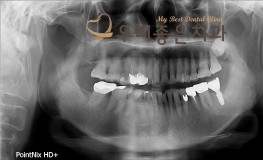

우리좋은치과 어금니 임플란트 치료(김**2018.8.10~2019.3.7)

No.245

임플란트

2019-03-07

1115